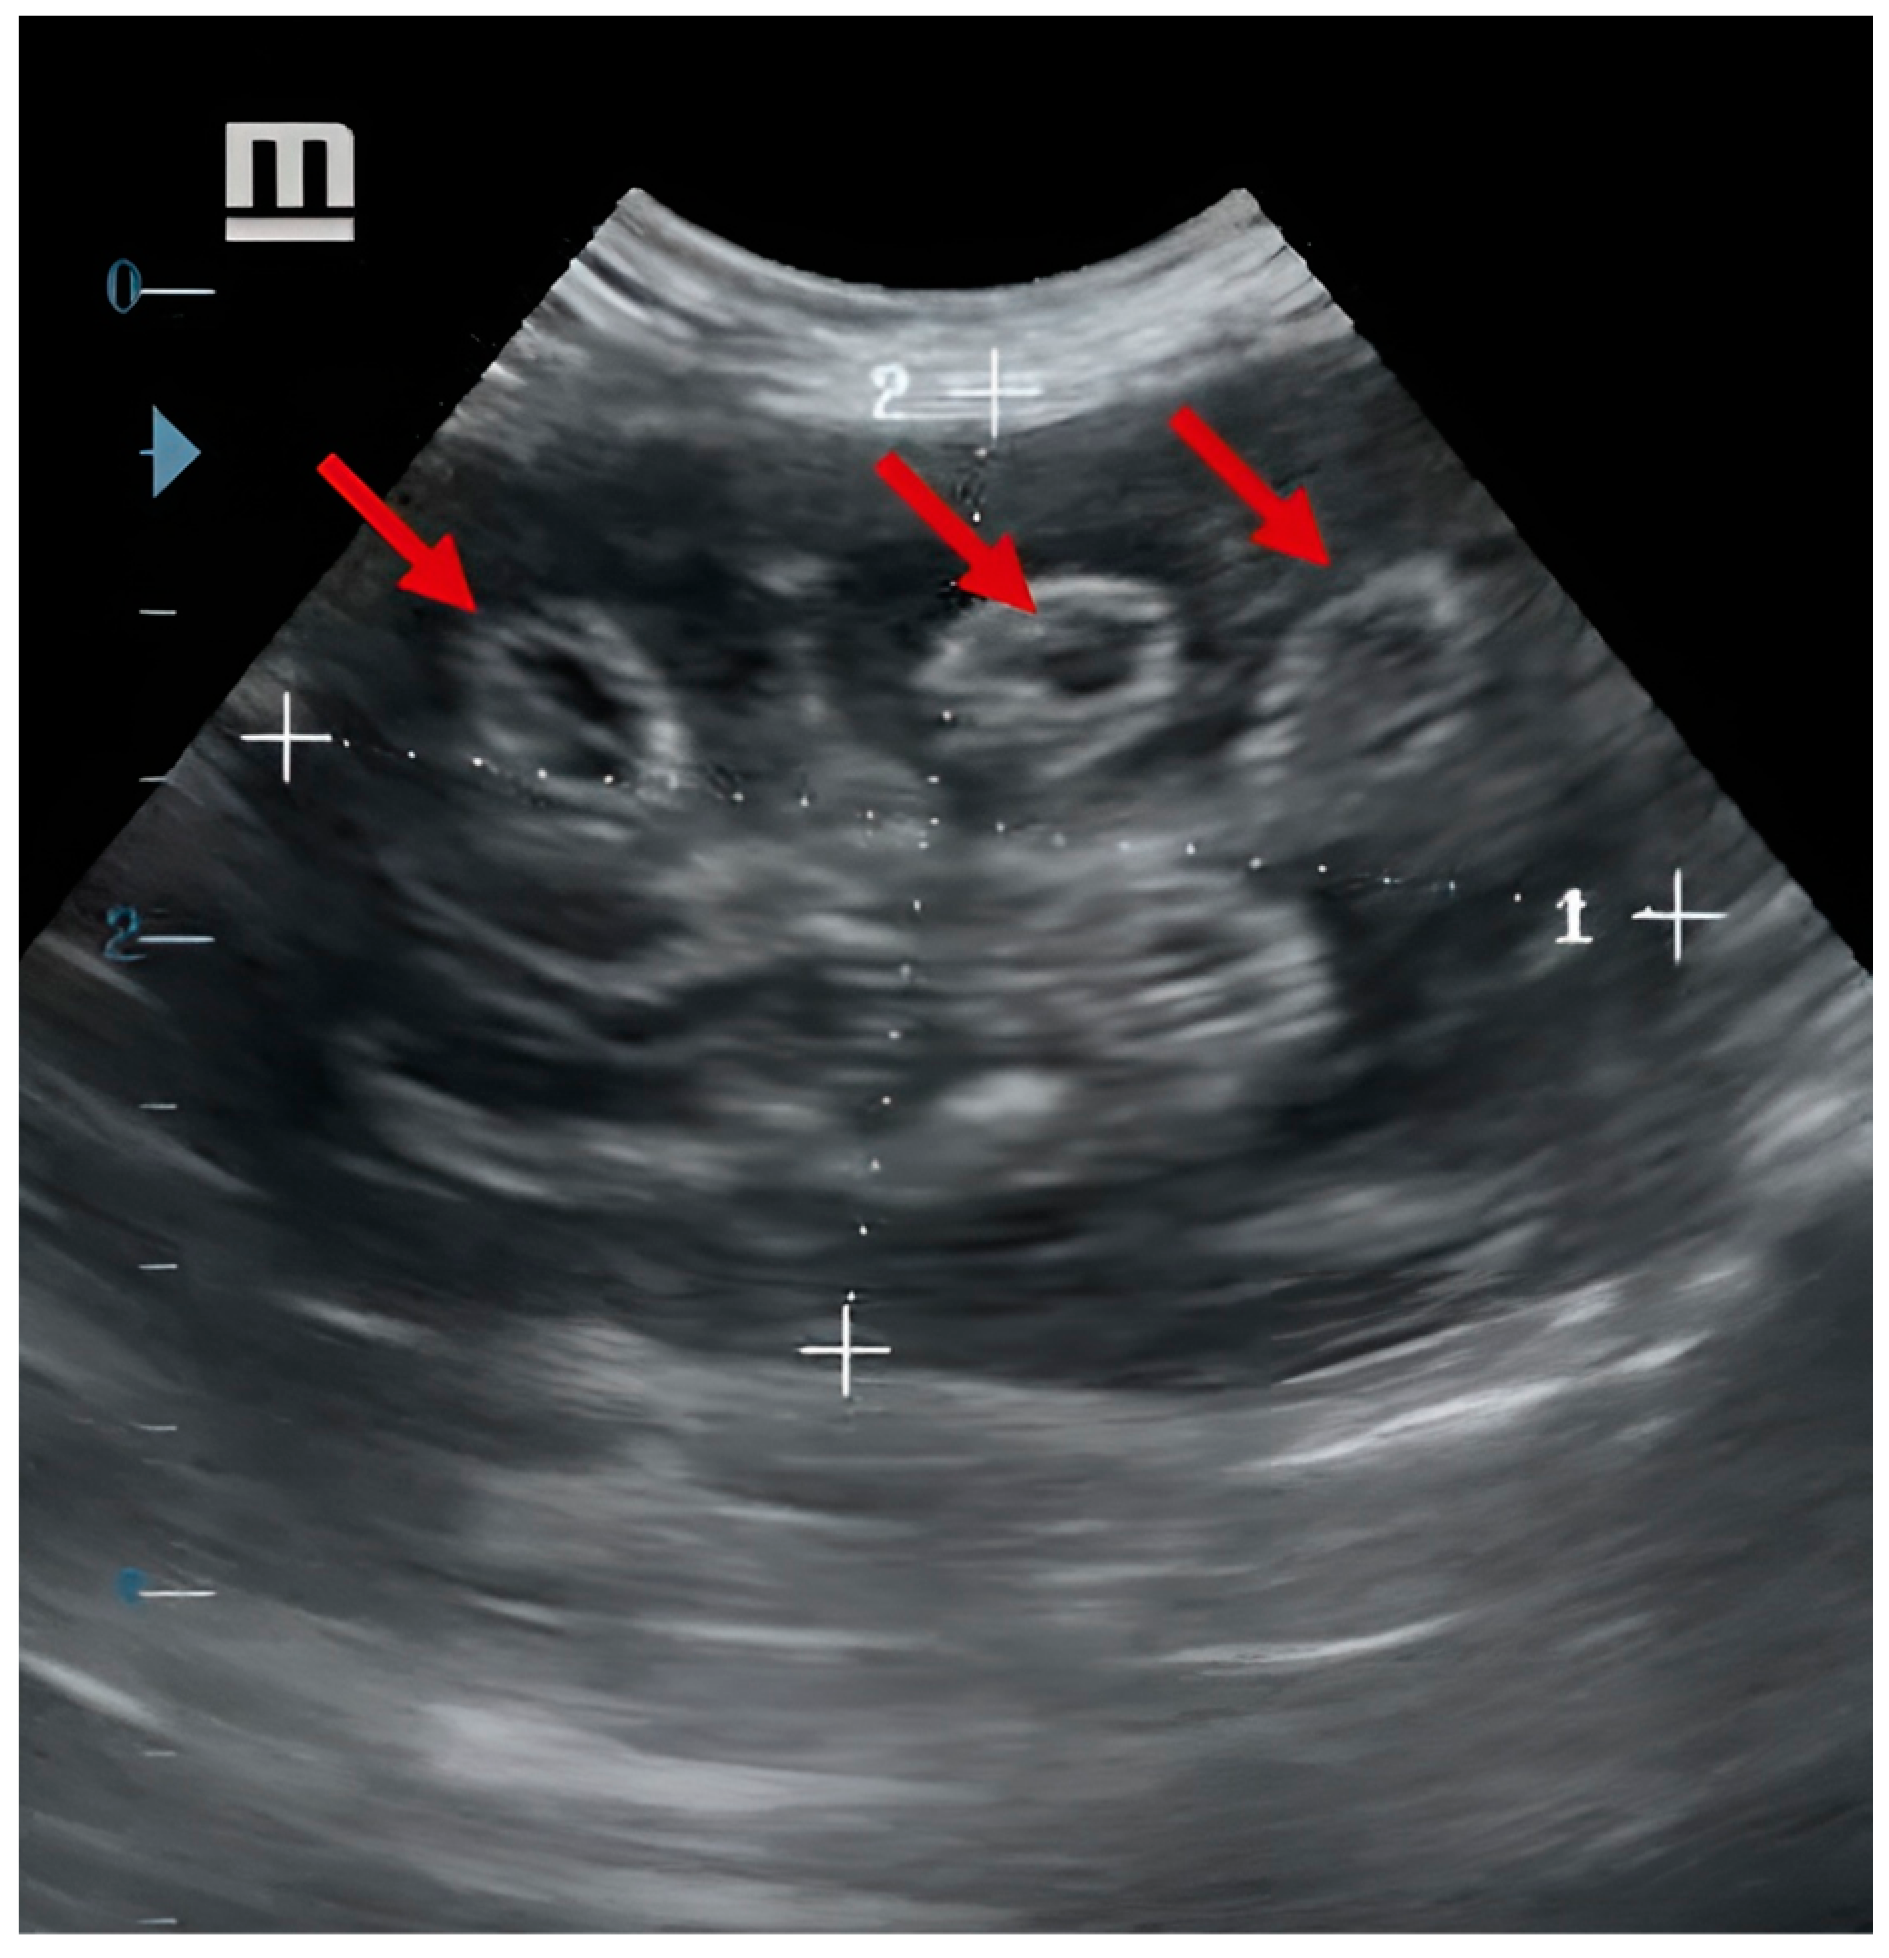

2. Case Report